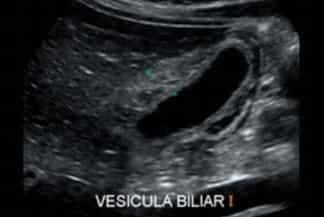

Descrição das figuras: Ultrassonografia de abdome. Vesícula biliar pouco distendida, com importante espessamento parietal, de aspecto estratificado e com aumento de fluxo ao Doppler colorido. Ausência de cálculos. Os achados podem representar colecistite alitiásica.

Exames de imagem: L embrando que, diante da suspeita de doença das vias biliares, os exames de escolha são ultrassonografia de abdome ou ressonância magnética (colangiorressonância). O paciente deve estar em jejum de cerca de 3-4 horas.

• Ultrassonografia de abdome: A presença de cálculos na vesícula biliar (colelitíase ) associado a sinal de Murphy ultrassonográfico positivo praticamente define o diagnóstico de colecistite aguda;